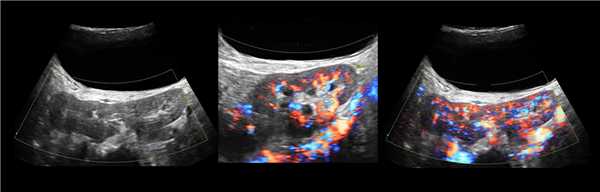

Клинический пример из второй группы. Пациент К. перенес операцию пересадки почки от живого родственного донора. Трансплантат в левой подвздошной области. Индекс резистентности в междольковых артериях составил 0,70 (рис. 5). В сегментарных артериях индекс резистентности составил 0,66 (рис. 6). Показатели жесткости паренхимы почечного трансплантата при режиме УЭСВ составили от 31,6 до 36,9 кПа (рис. 7-9).

Рисунок 7. Исследование в режиме ультразвуковой эластографии сдвиговой волны у пациента К.: жесткость паренхимы в зоне медиального края почечного трансплантата 36,9 кПа

Рисунок 8. Исследование в режиме ультразвуковой эластографии сдвиговой волны у пациента К.: жесткость паренхимы в зоне нижнего полюса почечного трансплантата 34,7 кПа

Рисунок 9. Исследование в режиме ультразвуковой эластографии сдвиговой волны у пациента К.: жесткость паренхимы у верхнего полюса почечного трансплантата 31,6 кПа

При снижении скорости кровотока и повышении индекса резистентности до 0,70 и более, как в первой, так и во второй группах, показатели УЭСВ составили от 28,00 до 39,45 кПа. Повышение жесткости паренхимы почечного трансплантата, на наш взгляд, связано с начавшимися изменениями (фиброза) в паренхиме почки. При повышении индекса резистентности более 0,70 показатели жесткости паренхимы при УЭСВ является дополнительным критерием, позволяющим оценить функциональное состояние почечного трансплантата. Ультразвуковая эластография ― новая развивающаяся методика, чувствительность, специфичность и точность которой увеличиваются при комплексном использовании с другими методами исследования. Анализ результатов проведенных исследований выявил значительные клинические возможности и перспективы применения метода ультразвуковой эластографии сдвиговой волны в оценке состояния почечного трансплантата. Полученные данные о диагностической точности метода позволяют использовать результаты в целях принятия решения о дальнейшем ведении пациента и тактике лечения [4].